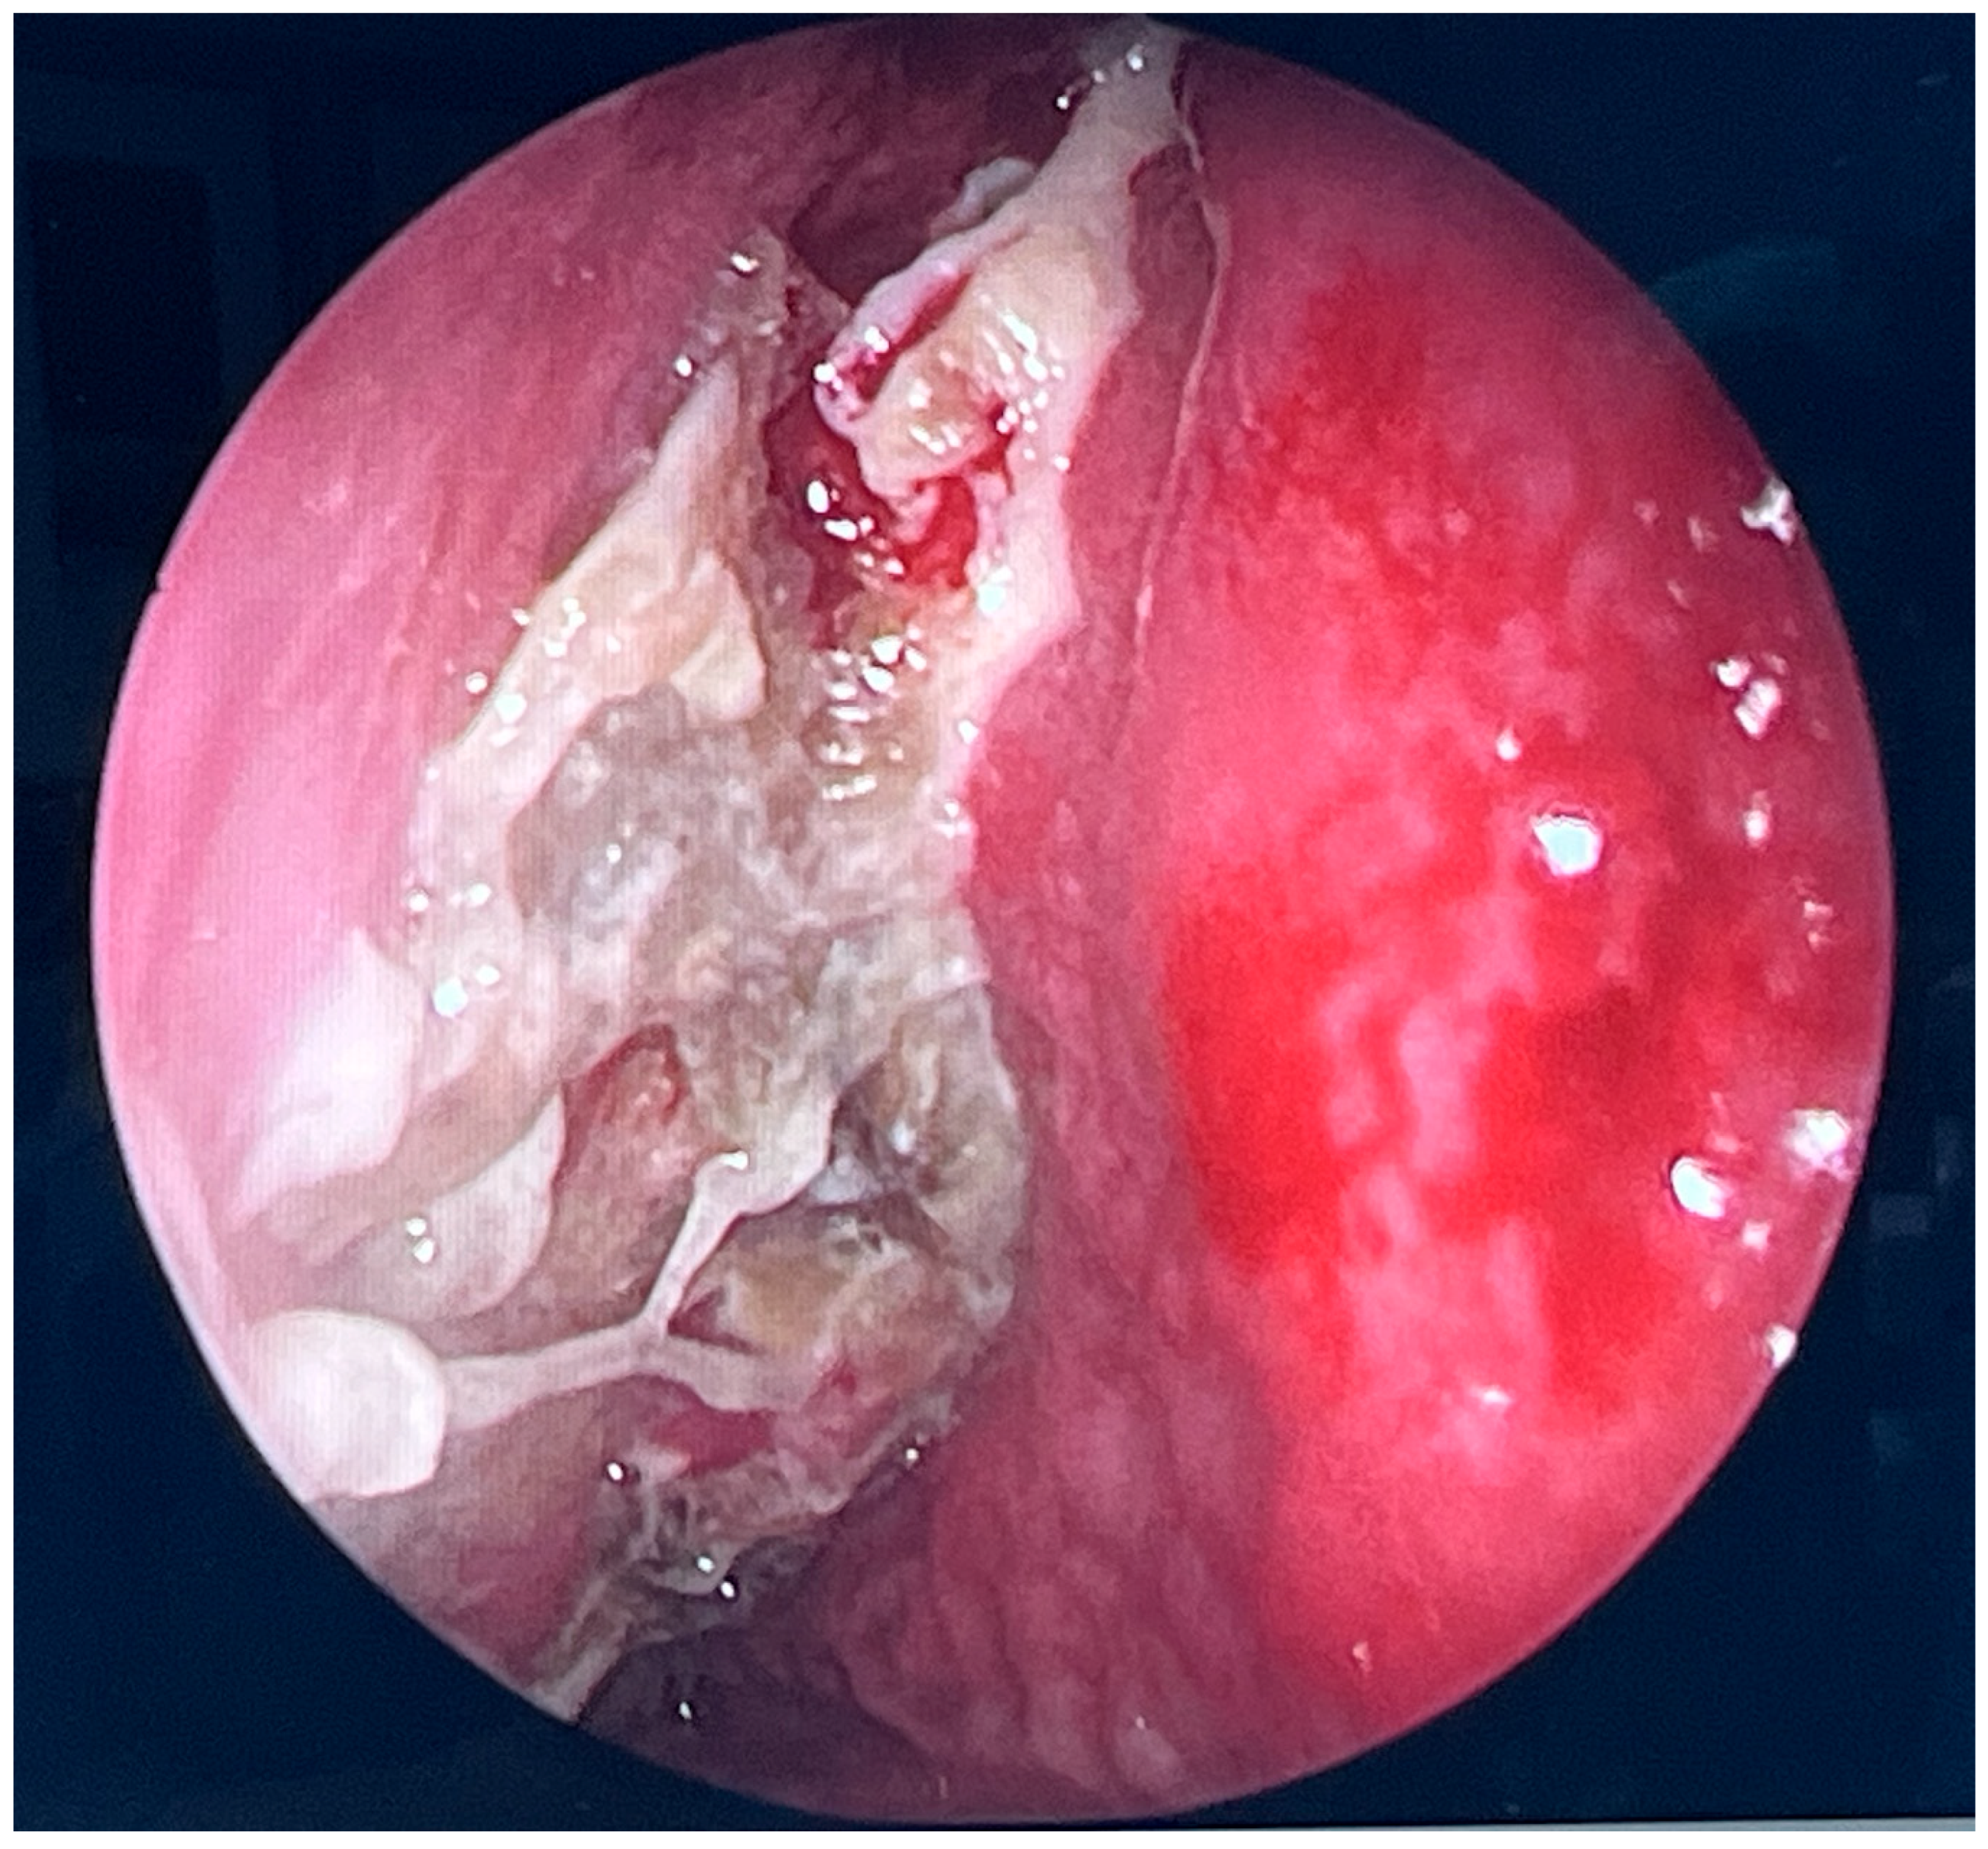

2.6. Postoperative Endoscopic Follow-Up

Postoperative endoscopic evaluations demonstrated a normal healing process, with no evidence of pathological secretions and maintained patency of the sinus outflow tracts (Figure 8). However, the mucosal lining of the maxillary and ethmoid sinuses remained thickened, consistent with ongoing post-inflammatory changes.

Fluticasone nasal spray and nasal irrigation were recommended together with continuation of oral posaconazole.

Figure 8. Endoscopic follow-up view 33 weeks after initial surgery. The openings of the maxillary sinus, orbit, and sphenoidal sinus are conspicuous. No inflammatory lesions or pathological discharge are present. The local condition appears unremarkable.